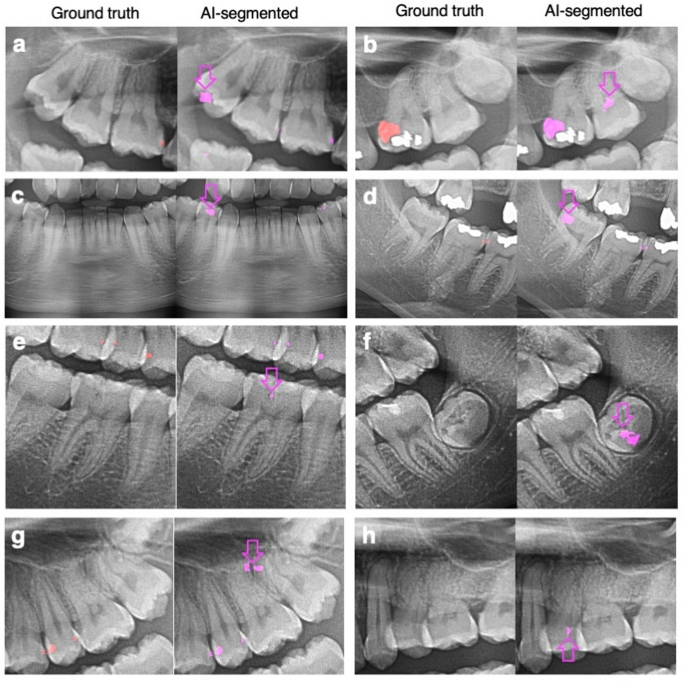

Despite the high level of agreement, some discrepancies emerged, particularly for enamel caries. The AI system tended to underestimate the number of enamel caries surfaces compared to radiologist evaluations (Table 3). This underestimation could be attributed to limitations in detecting smaller enamel lesions on radiographs compared to lesions with dentine or pulp involvement. Previous studies have also shown that even dentists demonstrate low sensitivity in detecting enamel caries on radiographs36,37. Furthermore, the AI model exhibited misclassifications in both directions, dentine caries misclassified as enamel caries (Underline number, Table 3; Fig. 6a and b), or enamel caries misclassified as dentine caries (Underline number, Table 4; Fig. 6c and d). In one case, the AI model predicted caries with pulp involvement as dentine caries (Underline number, Table 4; Fig. 6e). However, discrepancies were only observed in 5 out of 500 cases with no specific trend, and detecting caries on panoramic radiographs remains challenging even for experts19,38.

Examples of caries misclassification: cropped bitewing radiographs, cropped panoramic radiographs, ground truth, and artificial intelligence (AI)-segmented caries. (a) and (b) AI-predicted dentine caries as enamel caries; (c) and (d) AI-predicted enamel caries as dentine caries; (e) AI-predicted caries with pulp involvement as dentine caries.